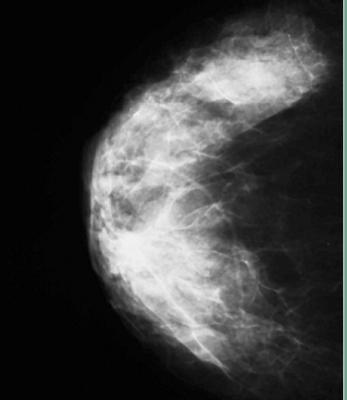

The accurate measurement of mammographic density offers the potential to improve breast cancer risk prediction and to tailor screening protocols according to risk, according to a study published in Breast Cancer Research (16:439 doi:10.1186/s13058-014-0439-1). The article, “Digital mammographic density and breast cancer risk: a case-control study of six alternative density assessment methods,” demonstrates a strong connection between breast density and breast cancer risk.

The study details the results of a comprehensive comparison of available mammographic density measurement tools and their ability to predict breast cancer risk. The performance of three area-based approaches (BI-RADS, the semi-automated Cumulus, and the fully-automated ImageJ-based approach) and three fully-automated volumetric methods (VolparaDensity from Volpara Solutions, Quantra from Hologic, and single X-ray absorptiometry (SXA)) were assessed in 3,168 digital mammography images. This included cancer cases diagnosed at Royal Marsden Hospital in London and normal mammograms from the England and Wales national mammographic screening program.

All six density assessment methods showed that percent density was inversely associated with age and body mass index (BMI), and certain reproductive factors. While all of the methods produced positive associations of density with risk, the association was highest for Volpara and Cumulus. Volpara and Cumulus were also the only tools that produced breast density measures for all images in the study, with other methods failing to produce readings for up to 11% of the participants. Women with the highest density had 8.26 times the risk of those with the lowest breast density as measured by Volpara on this dataset (the 95% confidence range was 4.28-15.96). The results also suggest that Volpara is better at identifying women at low risk than the other methods.